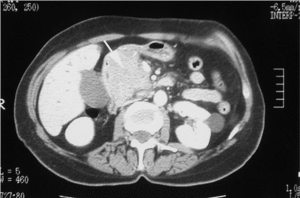

Varón de 48 años, alérgico a la procaína y al ácido acetilsalicílico, con historia de contactos sexuales de riesgo. Ingresó en nuestro hospital por un cuadro de 15 días de evolución de ictericia, coluria y acolia sin dolor abdominal, astenia intensa y pérdida de 5 kg de peso en los últimos 2 meses. En la exploración destacaban intensa ictericia mucocutánea y hepatomegalia dolorosa, palpándose adherida una masa dura y móvil. La analítica objetivó: hemoglobina de 13 g/dl, leucocitos de 2.400/μl (neutrófilos: 50,8%; linfocitos: 37,5%; monocitos: 7,5%; eosinófilos: 3,8%; basófilos: 0,4%); plaquetas de 36.000/μl, bilirrubina total de 14 mg/dl (valor normal: 0,20-1,20 mg/dl), aspartatoaminotransferasa de 11 U/l (4-38 U/l), alaninoaminotransferasa de 115 U/l (5-45 U/l), fosfatasa alcalina de 706 U/l (40-129 U/l) y gammaglutamiltranspeptidasa de 434 U/l (11-49 U/l). Se realizó serología para el VIH que resultó positiva con carga viral de 166.000 copias/ml, así como estudio de la población de linfocitos con CD4 de 48 copias/μl. La ecografía abdominal mostraba dilatación de la vía biliar intra y extrahepática y vesícula distendida (signo de Courvoisier). En la tomografía axial computarizada (TAC) abdominal se evidenciaba dilatación de la vía biliar intra y extrahepática hasta la región ampular, donde se observaba una tumoración de 2-3 cm de diámetro compatible con el diagnóstico de ampuloma, así como hepatomegalia discreta, esplenomegalia y signos de circulación colateral en hilio esplénico, adenopatías pequeñas alrededor del tronco celíaco, ligamento gastrohepático y cadenas ganglionares retroperitoneales de aproximadamente 1 cm y crecimiento de ambas glándulas suprarrenales con áreas hipodensas en su interior (fig. 1).

Figs. 1 y 2. TAC abdominal: dilatación de las vías biliares intra y extrahepática hasta la región ampular. Tumoración de 2 cm compatible con el diagnóstico de ampuloma. Hepatomegalia. Esplenomegalia. Adenopatías en el tronco celíaco, ligamento gastrohepático y cadenas ganglionares retroperitoneales.